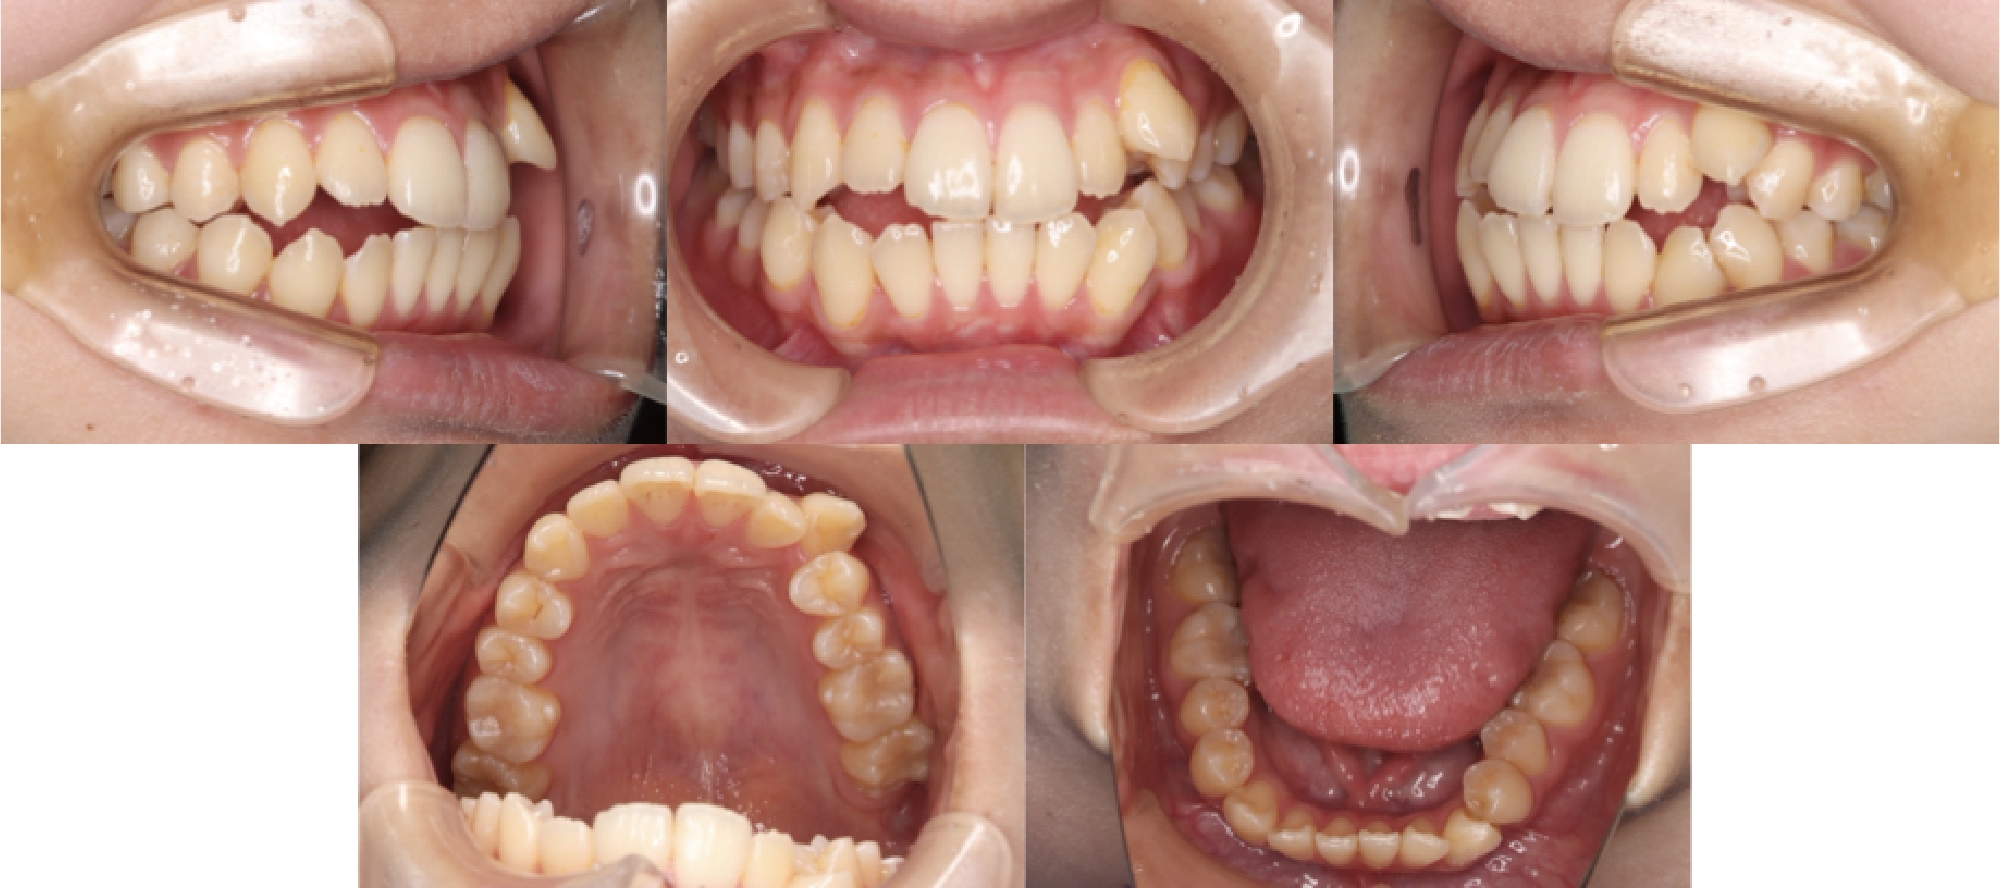

3DCTの治療例

治療終了時